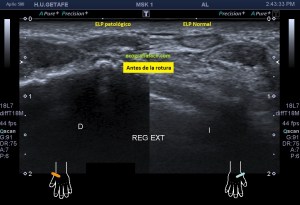

241. Rotura del Extensor Largo del Pulgar. Tercer Compartimento.

Tal como habéis decidido en Insta, voy a proceder a contaros el caso de esta semana. El paciente acude a la cita tarde. No afrontaba la exploración con una actitud positiva, pero la eco te coloca en tu sitio rápido y en este caso, me regaló un caso muy bonito que creo que te va a gustar.

Paciente que acude derivado del traumatólogo por una sospecha rotura del extensor del pulgar. Cuando posicioné al paciente para iniciar la exploración y le hice el interrogatorio habitual, me contó que desde un traumatismo donde se rompió las dos muñecas, tiene una incapacidad para estirar completamente el dedo pulgar a la altura de la interfalángica, no de la metacarpofalángica.

Lo que hace el tercer compartimento nada más desplazarnos hacia distal en el corte axial de la muñeca en su cara extensora y donde visualizamos el tubérculo distal separando ambos compartimentos 2 y 3, lo que hace el tercer compartimento, decía, es cruzarse por encima del dos para buscar diagonalmente su paso y su inserción en la cara dorsal del dedo pulgar. Si no entiendes esta anatomía, no vas a poder entender lo que pasa.

Lo que me llamó la atención fue que la parte superficial del segundo compartimento, correspondiente con el extensor largo del pulgar cruzando por encima del compartimento 2, era que estaba muy hipoecogénica y grande, así que una vez comprobado que los dos tendones del compartimento eran normales, y sabiendo que el tercero pasa por encima para cruzarse buscando el primer dedo, lo que hice fue seguir el tercer compartimento y lo que ví era que estaba situado en su lugar junto al tubérculo de lister, proximalmente, que a su cruce por encima del compartimento dos, estaba hipoecogénico y gordo y que ya en la mano, por donde cruza buscando el primer dedo, no estaba o al menos no estaba íntegro.

En este recorrido encontré un muñón, que se observa perfectamente en longitudinal, y que correspondía con el extensor largo del pulgar a la altura de su recorrido.

3

En esta imagen quiero que te fijes en el segundo compartimento y como el extensor largo del pulgar pasa por encima, los dos tendones del compartimento dos cortados en eje corto y el del tercero, cortado, pero en un corte para-axial. Lo importante es que te fijes en la ecogenicidad de ELP, en la izquierda hiperecogénico, isoecogénico con el segundo compartimento, por tanto normal. En la derecha hipoecogénico y más gordo, patológico.

4

Seguimos avanzando hacia distal, seguimos observando las mismas diferencias en las imágenes comparativas. Imagen justo antes de la rotura.

5

En la rotura el tendón es muy pequeño, pero normal en la izquierda y en la derecha lo es igual de pequeño, pero aplanado y con la pérdida de la ecogenicidad normal.

6

Después de la rotura, avanzando a distal, el tendón retraído, hipoecogénico, mucho más grande que su comparativo contralateral.

7

Corte en eje largo correspondiente a la imagen 6, donde se ve claramente lo que pasa y es definitivo para el diagnóstico final.

En resumen, desde la imagen 3 a la 8 observas el recorrido ecográfico del tendón extensor del pulgar desde proximal hasta distal, pasando por el foco de rotura y terminando con el muñón en axial y en longitudinal según marcan los pictogramas.